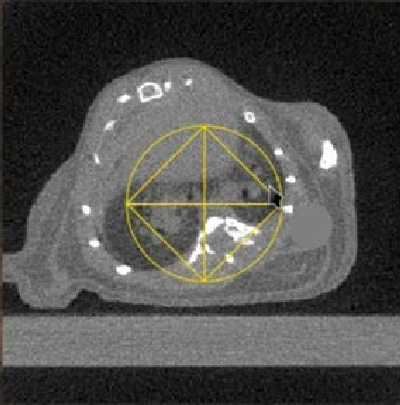

Fig 2. Reconstructed CBCT image of a mouse with lung fibrosis as viewed in the SmART+ software. (Left) Axial, (Center) Sagittal and (Right) Coronal views.